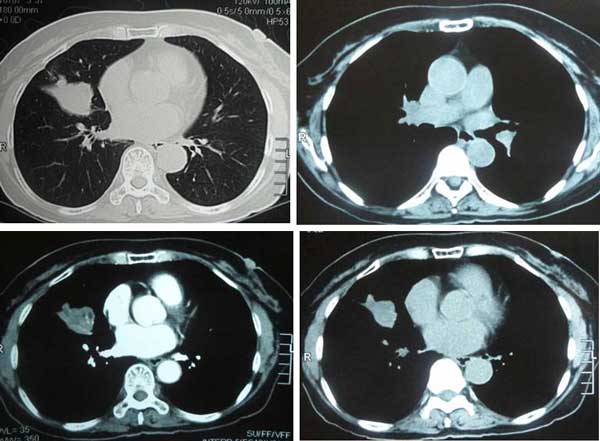

SC (H222) was 68 years old when her problem started. She is a non-smoker. She started to have coughs for the past six months. There were no other symptoms apart from pains at the right shoulder blade. A CT scan on 4 September 2008 showed a 3.0 x 4.75 x 3.0 cm opacity in right middle lobe of her lungs, suggestive of a neoplastic mass. Bronchial brushings showed moderately large neoplastic cells. Her blood test was normal, apart from a mildly elevated CEA (8.0).

CT scan on 4 September 2008.

SC underwent a CT scan of her brain and abdomen and these were normal. Her bone scan was negative for metastasis.

Her doctor suggested surgery since this was regarded as an early stage lung cancer, Stage 1B. Surgery was done on 29 September 2008 but it was aborted – an open and close case. The cancer had spread to the back of the chest wall and was now considered a Stage 4 lung cancer. The doctor suggested chemotherapy and said that without this treatment she would only have six months to live. SC declined chemotherapy. Her sister died one year after undergoing surgery, chemotherapy and radiotherapy for her breast cancer.